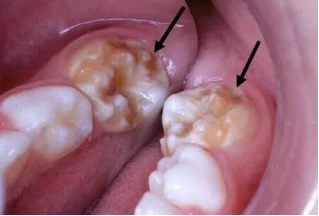

双排队形

现在很多孩子换牙的时候会出现“双排牙”:新牙和旧牙排成两排,同时出现在口腔里。这种情况叫做乳牙滞留,俗称“双排牙””,简单来说就是旧的乳牙还没来得及脱落,新的恒牙就已经迫不及待的长出来了。

图片

出现双排牙,提前拔除滞留的乳牙有利于新牙尽早的排齐,同时也便于清洁尤其是上颌的双排牙,应尽早拔除滞留乳牙,避免造成前牙反颌。因此,如果孩子出现了双排牙情况,是时候去拜访一下牙医了。